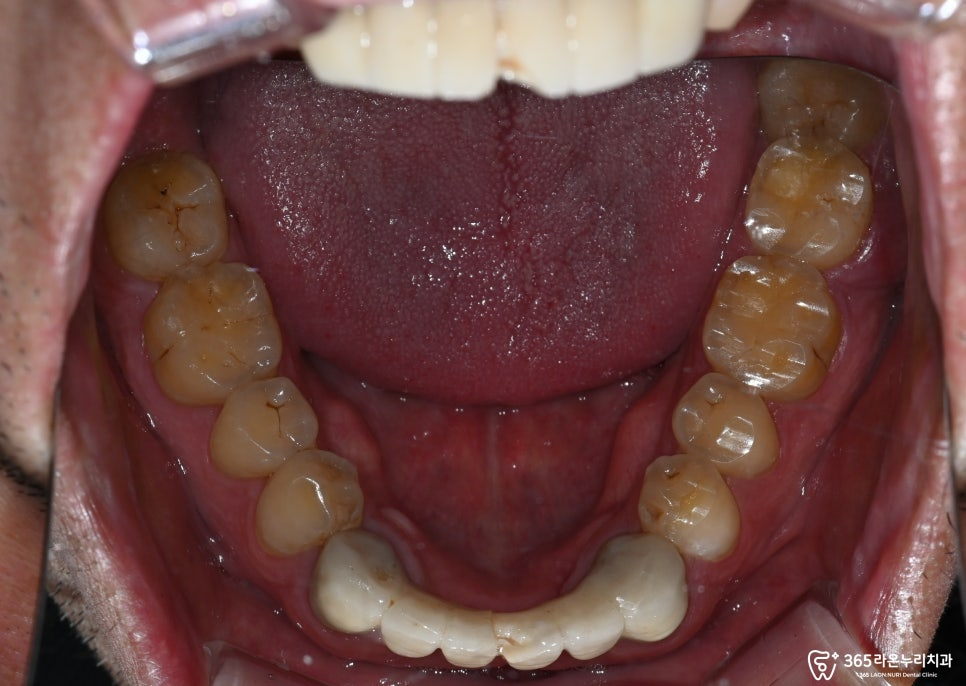

먼저 구내 사진을 보겠습니다.

구내사진을 보면

육안으로 파절부위는

보이지 않았습니다.